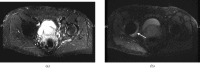

A variety of techniques are now available to directly or indirectly detect signal from tissues, fluids and materials that have short, ultrashort or supershort T₂ or T₂* components. There are also methods of developing image contrast between tissues and fluids in the short T₂ or T₂* range that can provide visualisation of anatomy, which has not been previously seen with MRI. Magnetisation transfer methods can now be applied to previously invisible tissues, providing indirect access to supershort T₂ components. Particular methods have been developed to target susceptibility effects and quantify them after correcting for anatomical distortion. Specific methods have also been developed to image the effects of magnetic iron oxide particles with positive contrast. Major advances have been made in techniques designed to correct for loss of signal and gross image distortion near metal. These methods are likely to substantially increase the range of application for MRI.